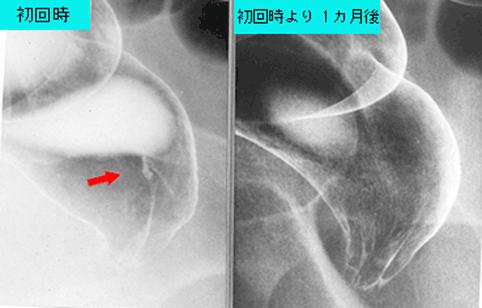

Rectal mucosal prolapse syndrome simulating small type 0-IIc (superficial depressed type) early rectal cancer.

Inflammatory or ulcerative disease / lesions/Rectal mucosal prolapse syndrome

Large intestine(Colon)/Rectum

X-ray

1 - 9